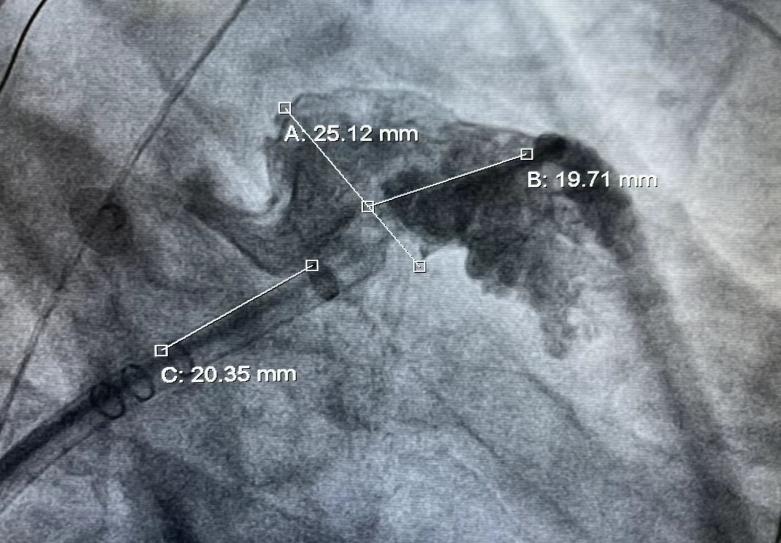

此例手术由韩稳琦博士和酉鹏华博士通过ICE指导下进行,通过ICE精准构建心脏模型、直视下穿刺房间隔,结合三维标测系统,精准、高效地完成双侧肺静脉隔离。后通过ICE及左心耳造影评估左心耳特征为下缘短,上缘折角大的短颈鸡翅型心耳,利用12F导引系统鞘管和猪尾导管在DSA肝位下同时造影,测量左心耳开口25.12mm,最大可用锚定区深度19.71mm,最终选择31mm规格watchman FLX封堵器的植入。ICE从不同角度检查即将释放的WATCHMAN FLX左心耳封堵器,观察封堵器位置、露肩、残余分流和压缩比情况,明确封堵器位置合理,无明显露肩,完全封堵无残余分流,封堵器位置良好。随后在ICE下观察及DSA透视下作牵拉试验,直到最后一次牵拉与前一次牵拉比较无位置改变,压缩比无明显变化,符合封堵器释放的“PASS”原则后完全释放封堵器。

2 DSA测量左心耳开口及深度